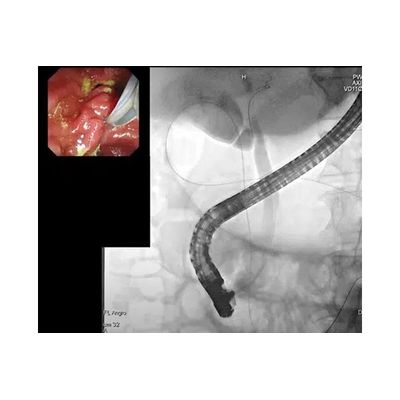

Endoscopic retrograde cholangiopancreatography (ERCP) is an imaging modality used for diagnosis and treatment of pathologies in the pancreatico-biliary system. Recent developments in the field of medical image analysis and artificial intelligence (AI) can be used to improve ERCP procedural outcomes. Here is how we use AI in Diagnostic ERCP.

The first navigational challenge of ERCP is inserting the guidewire into the Common Bile Duct (CBD) through the Major Papilla, while avoiding the pancreatic duct. This is done using the live-video image from the endoscopic camera, and X-ray verification using dye injections.

Threading a wire through a narrow opening using 2D images can be difficult. 3D reconstruction of the endoscope or the X-ray images, using advanced image analysis algorithms, adds the depth dimension to the process, increases the real 3D structure perception which contributes to shorten the procedure time, and reduce bowel perforations.